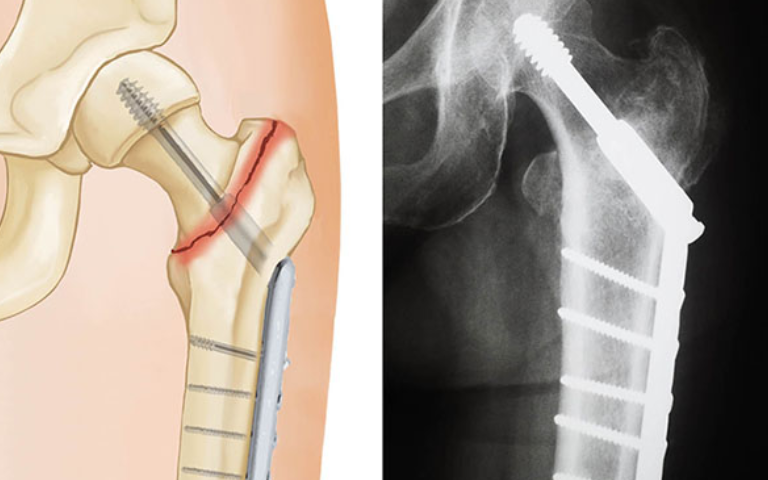

Surgical treatment options vary based on fracture type and patient needs. Common procedures include internal fixation with screws or plates, partial hip replacement, or total hip replacement. Each operation aims to stabilise the bone, restore leg function, and allow early mobilization. Treatment is personalised by an experienced Orthopaedic Specialist in Islamabad to match the patient’s health, age, and activity goals.